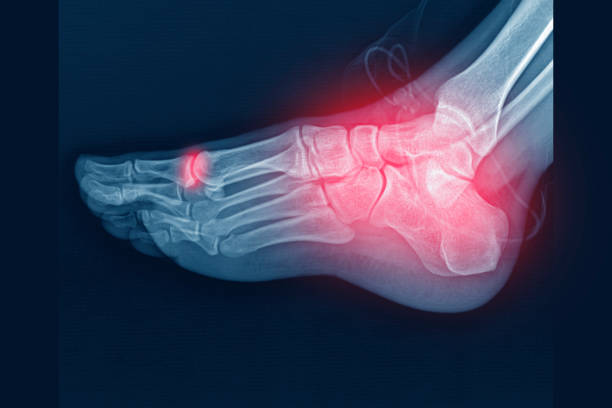

류마티스 관절염은 관절의 통증과 염증을 동반한 만성 질환으로, 주로 손목, 손가락, 발목, 발가락 등의 작은 관절에서 발생합니다.

류마티스 관절염의 초기증상 중 가장 흔한 증상은 통증입니다. 관절 주위의 인대, 힘줄, 근육에 염증이 생기면서 통증이 발생하며, 특히 아침에 관절을 움직일 때나 장시간의 휴식 후에 증상이 더욱 악화될 수 있습니다.

류마티스 관절염 초기에는 관절 주위의 염증으로 인해 손발이 부어오를 수 있습니다. 부종은 주로 관절 주위의 소프트 티슈에 액체가 모이면서 발생하며, 아침에 특히 심할 수 있습니다. 이러한 부종은 통증과 함께 관절의 움직임을 더욱 제한합니다.